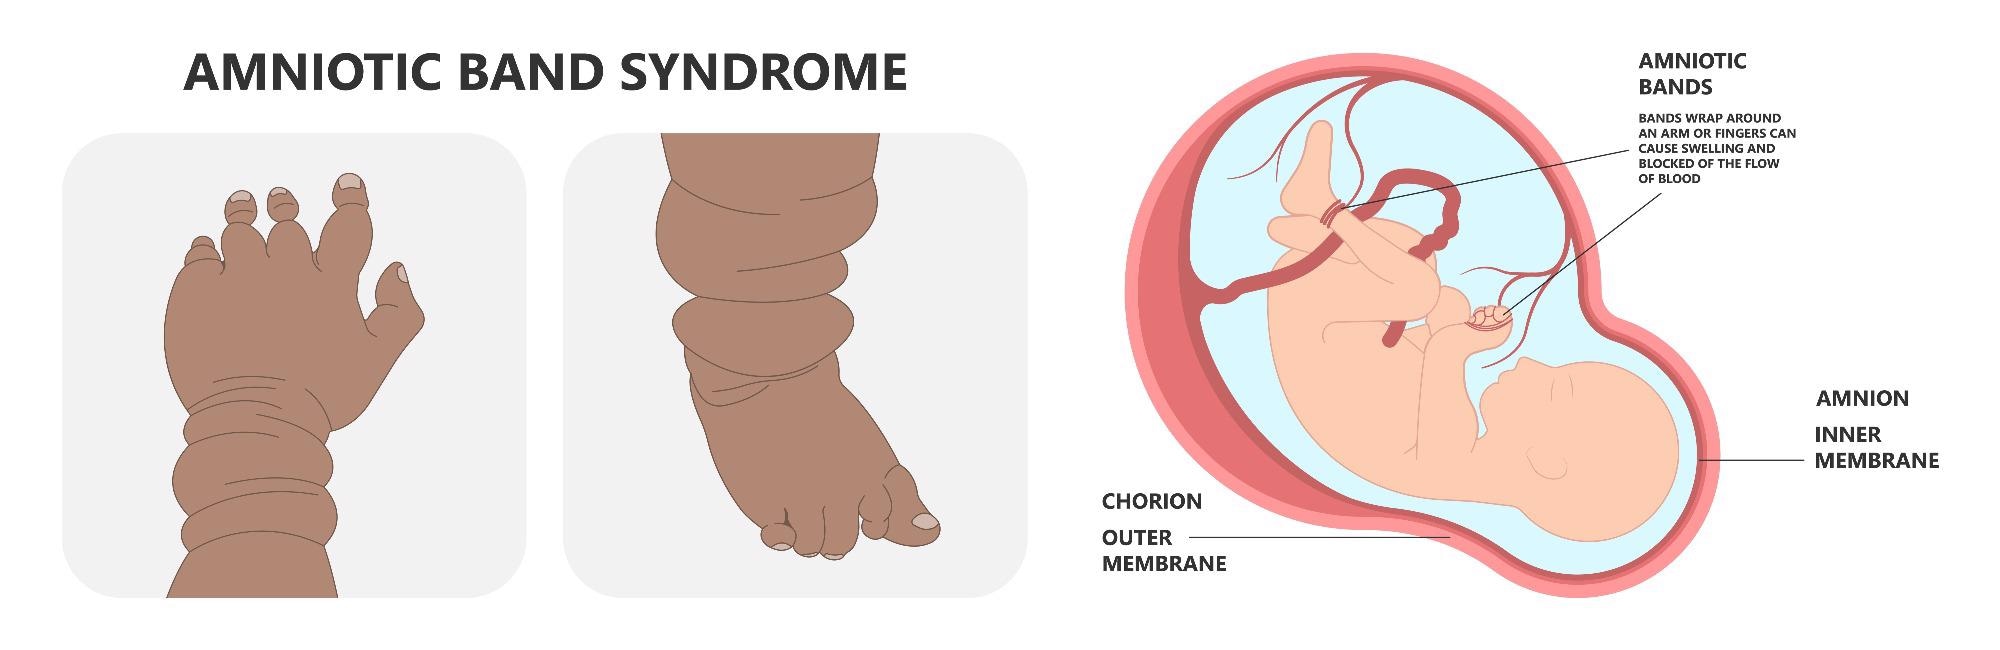

During pregnancy, the lining of the amniotic sac gets damaged leading to amniotic band syndrome. Due to this, the tissues divide and form string-like structures called strands that entangle the fetus and other developing parts of the body. As a result, blood flow is constricted.

This prevents the fetus from growing correctly by constricting blood flow and results in a variety of birth abnormalities. Amniotic band syndrome can range in severity from a single, isolated issue to several, disfiguring sequelae. Arms and legs are the most commonly affected areas of the body.

The majority of infants with amniotic band syndrome have deformities in their arms and legs, as well as their fingers and toes. One or more limbs may be afflicted. The upper limbs are more commonly damaged than the lower limbs. ABD may lead to the formation of a minor dent around a finger or limb.

Deeper bands, on the other hand, can cause major swelling, shut off blood supply, or prevent that region of the body from growing properly. If a band is too tight, it can result in amputation in utero (before delivery).

The type of malformation caused by ABS is determined by the area of the body involved. Atypical clefts of various types, including those affecting the eyes, nose, and ears, may develop if it affects the orofacial region. Constriction rings, amputations, aberrant dermatoglyphs, pseudo syndactyly, and clubbed feet are among the limb anomalies.